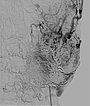

Auffüllung des gesamten Nidus der AVM mittels Ethylen-Vinyl Alkohol-Kopolymer, das in dem hier dargestellten Röntgenbild (a.-p.) als schwarzer, netzartiger röntgendichter Ausguss (sogenannter Cast) innerhalb der verschlossenen AVM-Gefäße sichtbar wird.

Auffüllung des gesamten Nidus der AVM mittels Ethylen-Vinyl-Alkohol-Kopolymer, das in dem hier dargestellten Röntgenbild (seitliche Ansicht) als schwarzer, netzartiger röntgendichter Ausguss (sogenannter Cast) innerhalb der verschlossenen AVM-Gefäße sichtbar wird.